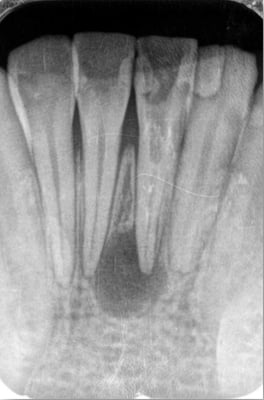

歯根端切除術 Apicopectomy

上顎中・側切歯 root endo sealing

coming soon!